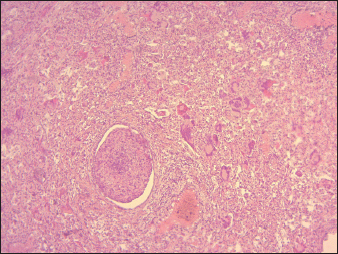

The most important histopathological lesions were observed in the lungs, intestines, spleen, and lymph nodes. The lungs had the most severe histopathological abnormalities, which were characterized by edema in the alveoli combined with fibrinous exudate infiltration of mononuclear cells and thickening of the interalveolar septa (Fig. 5), presence of syncytial cells (Fig. 5). Intestines revealed ulcerations of the intestinal mucosa in some areas, loss of intestinal villi with the intestinal crypts appearing clear and loss of epithelium, the lamina propria was infiltrated with Macrophages and lymphocytes, the duodenum, jejunum, and ileum showed extensive effusion of the submucosa with progressive thickening of the submucosal layer (Fig. 6). Degeneration and necrosis of glandular epithelial cells were also seen.

The lymphoid follicles in Peyer’s patches exhibited destruction, characterized by lympholysis (Fig. 6). MLNs showed severe congestion, hemorrhage, swelling, and depletion of lymphoid cells (Fig. 7). Additionally, other lesions are marked by the depletion of lymphocytes in the spleen, and histopathological changes in the heart, including congestion and hemorrhages. The thymus showed severe depletion of lymphocytes and severe congestion (Fig. 8). Furthermore, the liver showed severe congestion and hemorrhage with hepatocyte atrophy accompanied by the expansion of the sinusoidal spaces. The kidney exhibited slight glomerular atrophy, significant necrosis, and loss of epithelium in the renal tubules.

Fig. 5. Pulmonary parenchyma severely infiltrated with inflammatory cells (interstitial pneumonia) with a group of syncycial cells associated with severe bronchiolitis (40X, H&E).

Our study revealed the presence of severe broncho-pneumonia, characterized by thickening of the interalveolar septa and the presence of syncytial cells. These findings can be attributed to the extensive replication of the virus in the respiratory epithelium. The thickening of the alveolar septa indicates substantial tissue damage, which is likely attributable to direct viral cytopathic effects and the host’s immune response. Such damage may impair gas exchange, potentially leading to respiratory distress and in more severe cases, hypoxemia and death. PPRV is known to produce syncytia (fusion of cells) in Vero cells, a cell line derived from African green monkey kidney epithelial cells (Osman et al., 2019). Macroscopic findings of the lungs, trachea, and small intestine found in this study are mostly similar to those observed in previous studies reported by Begum et al. (2021) and Maina et al. (2015) in experimentally infected goats and sheep and Ugochukwu et al. (2019) in naturally infected sheep and goats.